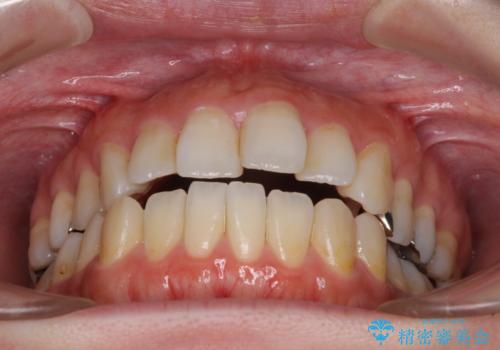

出っ歯と奥歯の欠損 ワイヤー矯正とインプラント治療

- 口元の突出感と奥歯の欠損を気にして来院された患者様です。

口元の突出感改善には、上下左右の第一小臼歯4本を抜歯し、奥歯の欠損部には矯正治療の途中でインプランを埋入していくこととしました。

矯正治療の後半にインプラント埋入を行うことで、トータルの治療期間を短縮することができました。